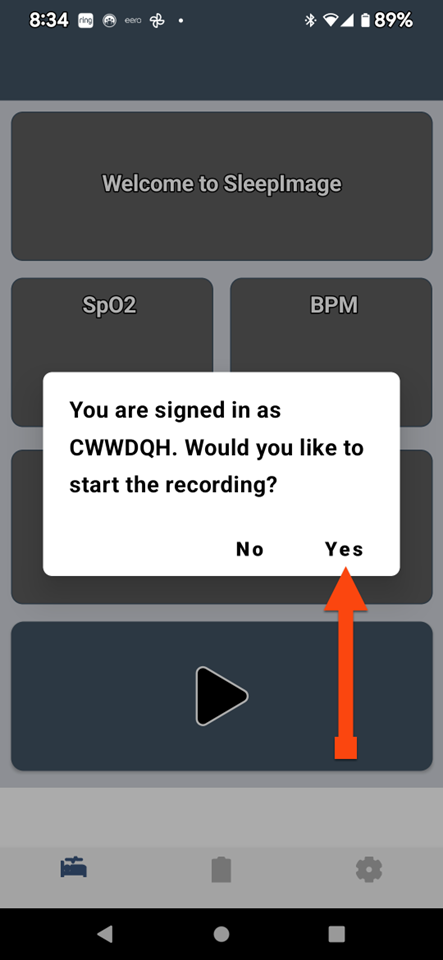

SLEEPIMAGE APP (Android)

SLEEPIMAGE APP (Android)

SLEEPIMAGE APP (Android)

SLEEPIMAGE APP (Android)

SLEEPIMAGE APP (Android)

SLEEPIMAGE APP (Android)

SLEEPIMAGE APP (Android)

SLEEPIMAGE APP (Android)

SLEEPIMAGE APP (Android)

SLEEPIMAGE APP (Android)

SLEEPIMAGE APP (Android)

SLEEPIMAGE APP (Android)

SLEEPIMAGE APP (Android)

SLEEPIMAGE APP (Android)

SLEEPIMAGE APP (Android)

SLEEPIMAGE APP (Android)

SLEEPIMAGE APP (Android)

SLEEPIMAGE APP (Android)

SLEEPIMAGE APP (Android)

SLEEPIMAGE APP (Android)

SLEEPIMAGE APP (iPhone)

SLEEPIMAGE APP (Android)

SLEEPIMAGE APP (Android)

SLEEPIMAGE APP (Android)

SLEEPIMAGE APP (Android)

SLEEPIMAGE APP (Android)

SLEEPIMAGE APP (Android)

SLEEPIMAGE APP (Android)

SLEEPIMAGE APP (Android)